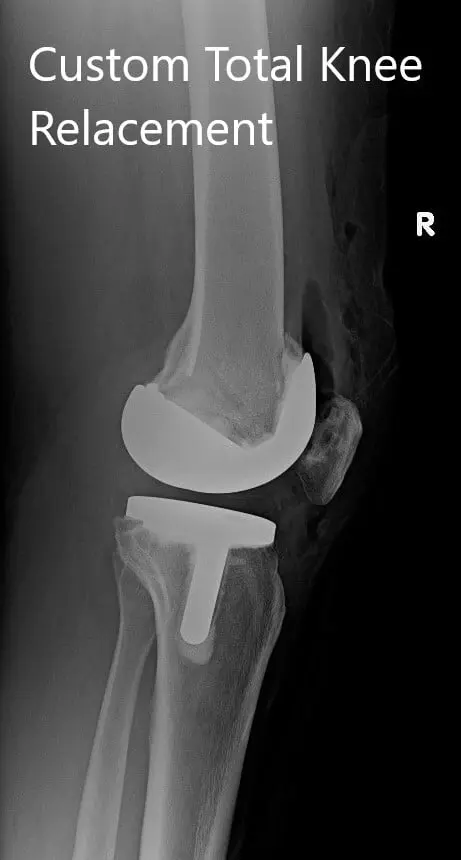

Postoperative X-ray showing AP and lateral images of the right knee

IMPLANTS USED: Custom femur with a Custom tibia with 10-mm polyethylene insert with a 32-mm x 6-mm patella.